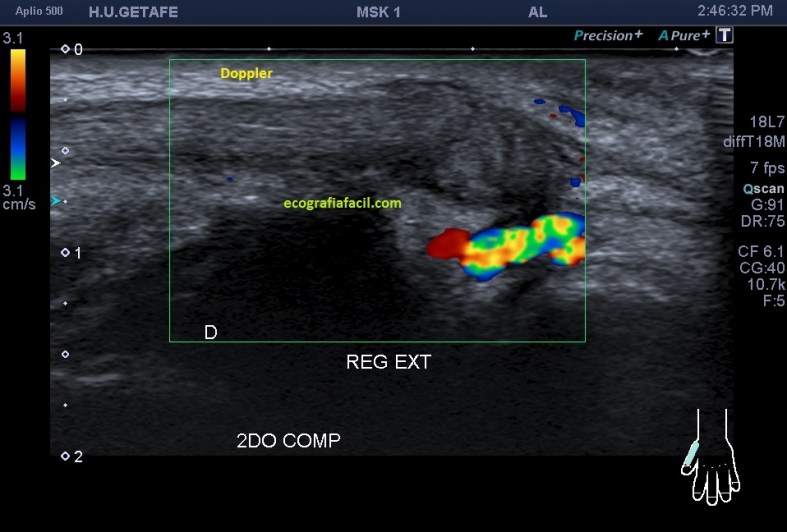

Comprobar con doppler para ver si hay actividad, que no la hay y es que la lesión no es reciente y esto podría explicar tal circunstancia.